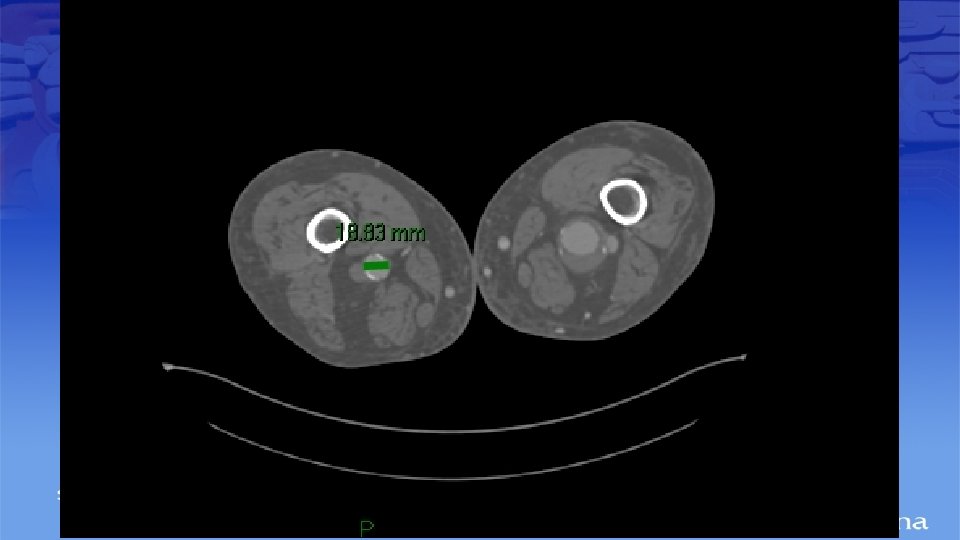

Impresión Diagnóstica • IDX: Aneurisma Poplíteo bilateral

Diagnostico • Ultrasonido Doppler, Angiotac, angioresonancia • Arteriografía es mas apropiada para sintomatología aguda